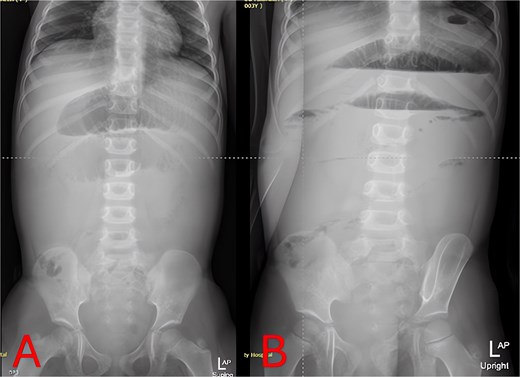

On hospital Day 2, an abdominal MRI without contrast confirmed marked fluid-filled small-bowel loop dilation and a focal transition point in the right lower quadrant (Fig. 3A). Axial sequences demonstrated a periappendiceal fluid collection with mesenteric edema and a possible appendicolith (Fig. 3B). A sagittal plane showed the abscess tracking into the pelvis (Fig. 3C), indicating perforated appendicitis causing adhesive small-bowel obstruction.

MRI of the abdomen—identification of obstruction cause. (A) Coronal T2-weighted MRI showing multiple fluid-filled, dilated small-bowel loops and a focal right lower quadrant transition point. (B) Axial T2-weighted MRI demonstrating a periappendiceal abscess with mesenteric edema compressing adjacent ileal loops. (C) Sagittal MRI view highlighting appendiceal abscess boundaries and a possible appendicolith.

Imaging is critical to distinguish uncomplicated gastroenteritis from mechanical obstruction. While plain radiographs can confirm SBO (Figs 1 and 2), they may not reveal its cause. Although CT offers high sensitivity for appendiceal pathology, radiation exposure is a concern in young children. MRI without contrast provides a reliable alternative, demonstrating excellent diagnostic accuracy for pediatric appendicitis [7]. In our case, T2-weighted images identified a periappendiceal fluid collection, mesenteric edema, and an appendicolith (Fig. 3), guiding prompt surgical intervention.